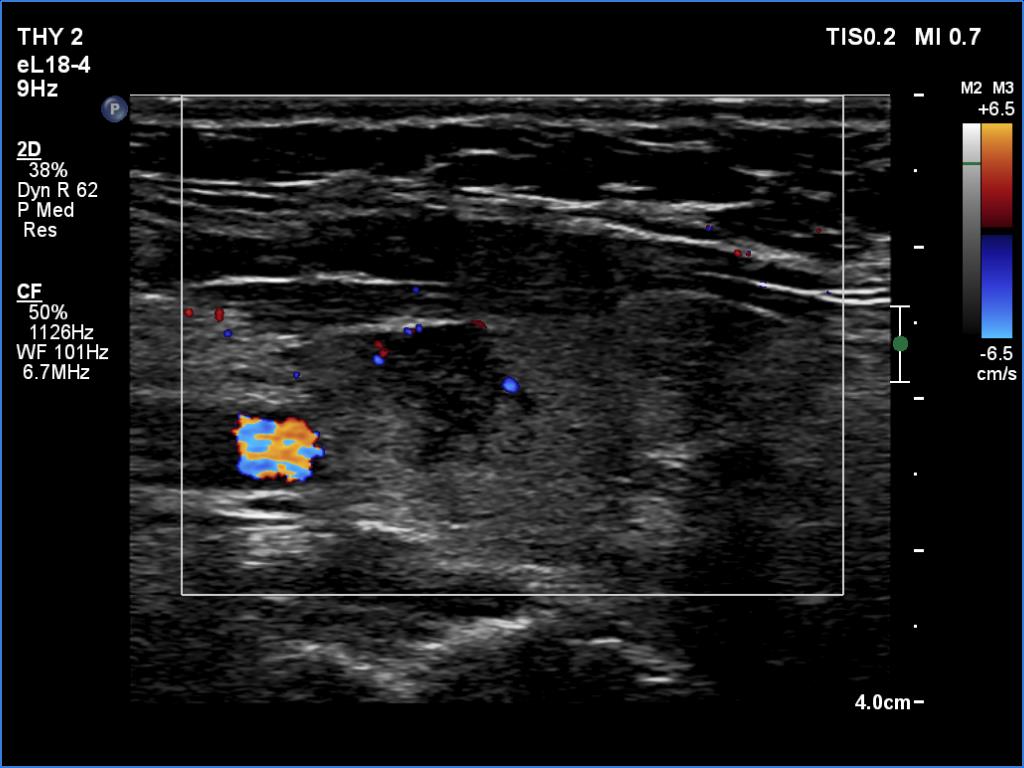

Left lobe, longitudinal scan, color Doppler mode. The lesion shows signs of intralesional vascularity.